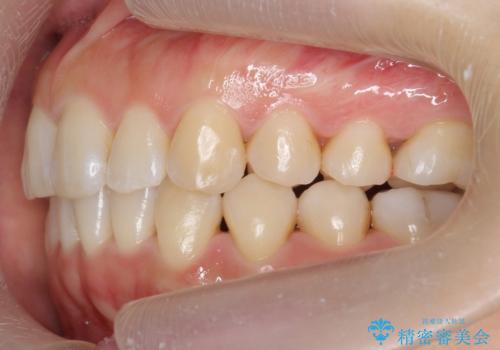

下の前歯のがたつき インビザラインで

- 前歯のがたつきを主訴に来院。

インビザラインで上下の前歯をわずかに削って並べました。

下の歯の叢生を並べると多少ブラックトライアングルがでることがあります。